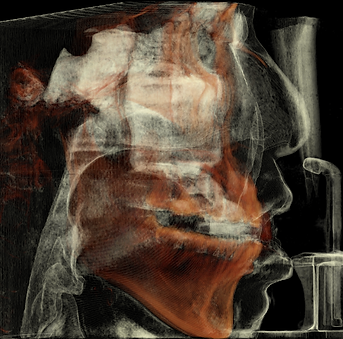

Inhaled airdensity

(lateral view)

before

after